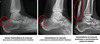

Sinal da dupla densidade na Fx do Calcâneo?

Demonstra que a porção lateral da faceta posterior foi fraturada, mas a parte medial está íntegra.